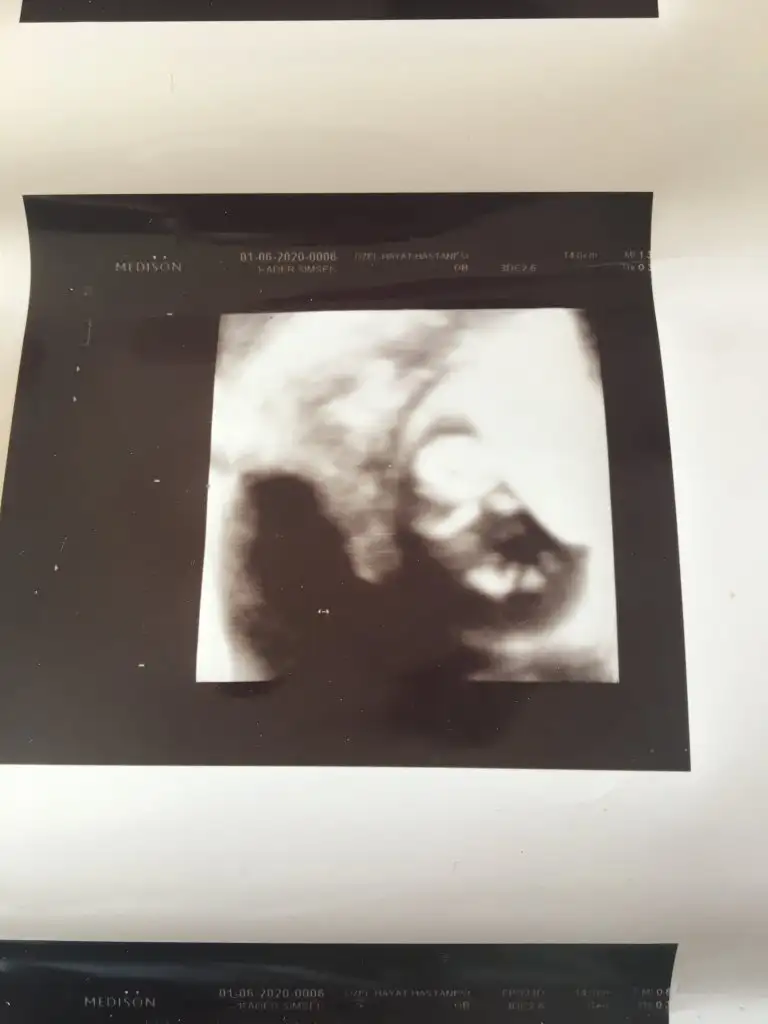

Erkek gibiMrb 11 haftalik anlayan arkadaslar rica etsem banada cinsiyet tahmini yapabilirmi cok merak ediyoruz

Kız canım %90Mrb 11 haftalik anlayan arkadaslar rica etsem banada cinsiyet tahmini yapabilirmi cok merak ediyoruz

Nuba goremi soylediniz bu aralar herkes erkege bemzetiyor tabi onceligimiz saglikli olmasiKız canım %90

Erkek gibi canım çıkıntı varMerhaba rica etsem cinsiyet tahmininde bulunabilir mısınız bugün 11 hafta+2 günlük

Eki Görüntüle 2640878 Eki Görüntüle 2640878 nub teorisinden anlayan varsa çok sevinirim :)